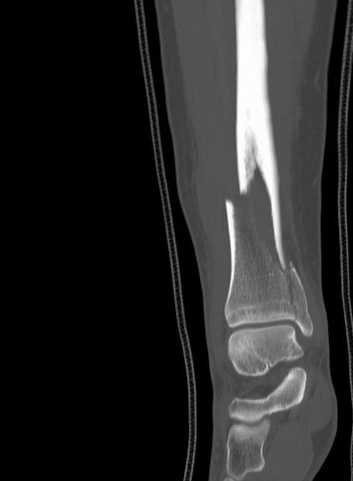

In 2020, I suffered a bad fall (who knew slipping off a not so outrageously tall boulder could be so consequential?) that left me unable to move my leg or stand at all, with the foot pointed in an unnatural direction. Eight firemen, an ATV ride with a gurney I was strapped into, and an hour-long ambulance ride later, I found out it was no minor break: I had a serious displaced tibia/fibula spiral pilon fracture. The rural hospital told me my leg looked like something seen in major car or skiing accidents, and after keeping me on a morphine drip overnight, they ended up declining to perform the surgery. They said it was too complex for them to feel confident handling.

My first surgery with Dr. Levine was an internal fixation to realign the bones and give me a chance to eventually walk again. I ended up with two metal plates and about a dozen screws. Seeing the post-op images of the repair confirmed what I already felt: surgery is absolutely a science but with masters like Dr. Levine, it's also an art. The recovery was tough, off my leg for months and isolated in a walk-up Brooklyn apartment, but Dr. Levine prepared me for that. He made it clear that the recovery would be hard, painful, and boring, but I'd get through it.